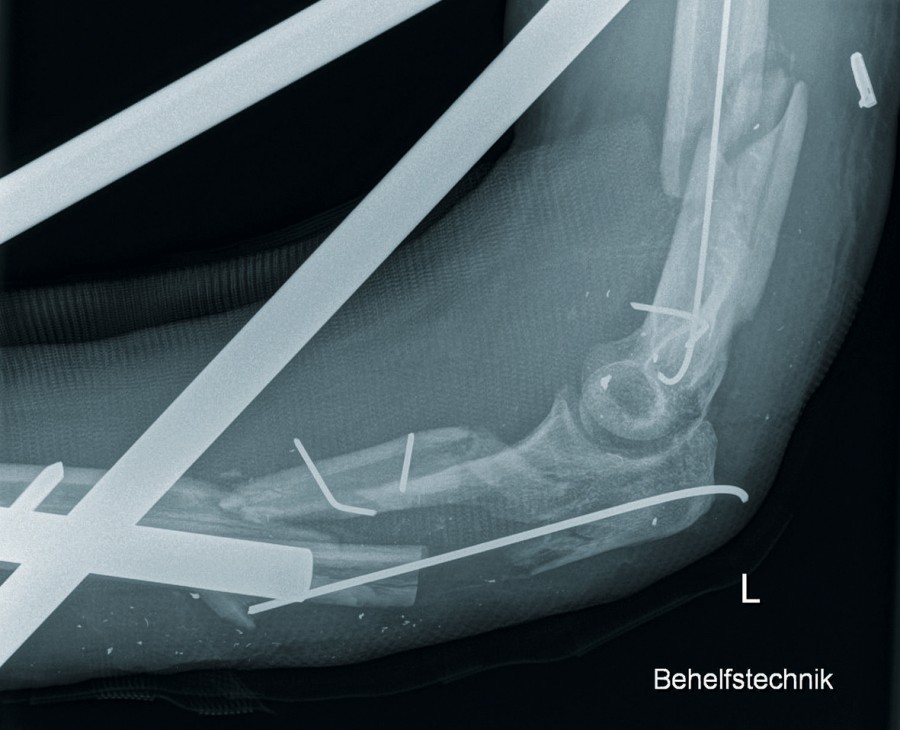

Ein 42-jähriger Patient erlitt im Ukrainekonflikt eine Blast injury infolge eines Granateinschlages in eine Haubitze, die er bediente. In Kiew erfolgte zunächst die Primärversorgung, bevor der Patient etwa einen Monat nach Verletzung zur weiteren Therapie nach Deutschland verlegt wurde. Bei Aufnahme zeigte sich folgendes Verletzungsmuster, siehe Abb. 5:

- Mehrfragmentäre Humerusfraktur links.

- Mehrfragmentäre proximale Ulna- und Radiusfraktur links mit persistierender Ellenbogenluxation.

- Partielle Radialisparese links.

- Mehrfragmentäre supracondyläre Femurfraktur links.

- Traumatische Fingeramputation D5 links.

- Multiple Weichteilverletzungen.

- Multiple Fremdkörpereinsprengungen im Bereich des Gesichtes und partiell des Auges.